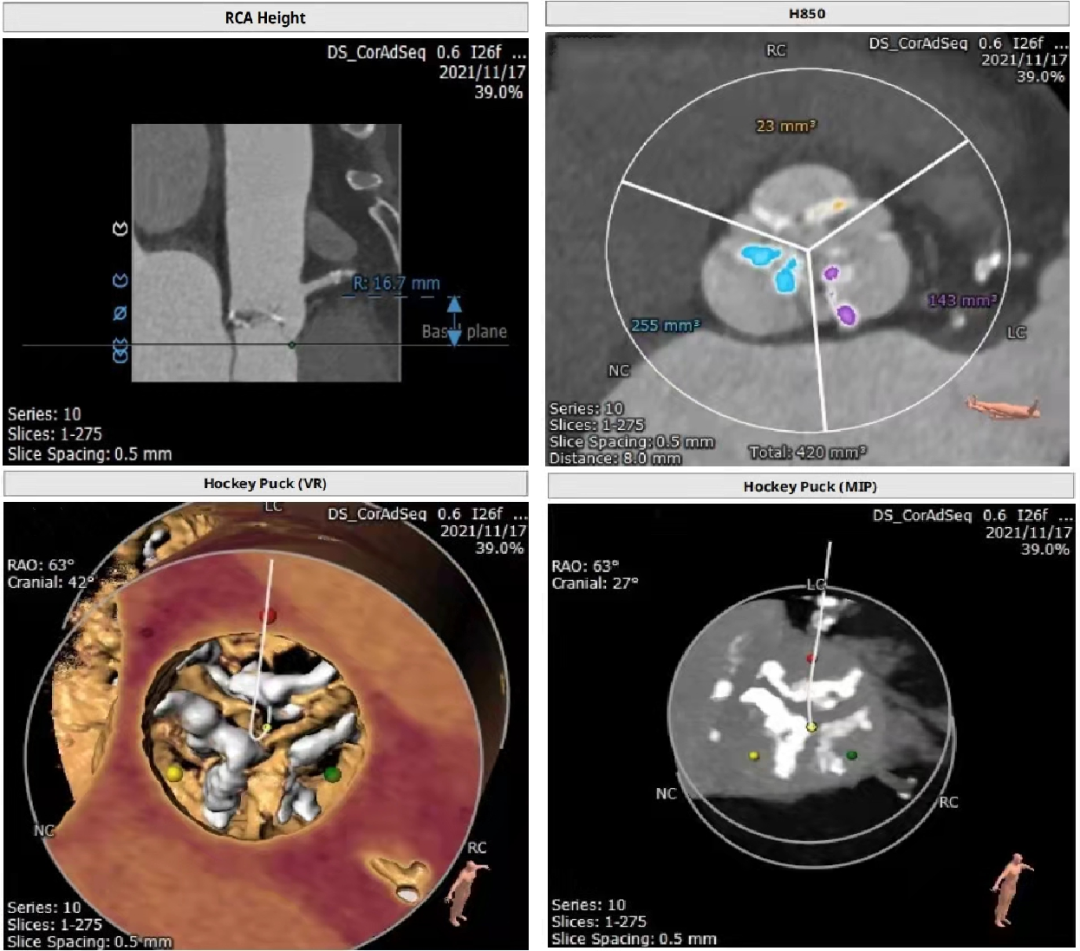

主动脉瓣CT评估

三叶瓣,瓣环径24mm,瓣环长短径分别为27.3*20.4mm,周长为75.5mm,面积为436.8mm²。左室流出道25.7mm,法式窦27.2mm*30.6mm*30.6mm,左冠高度19.3mm,右冠高度16.7mm,窦管交界 25.9mm,升主动脉直径29mm。